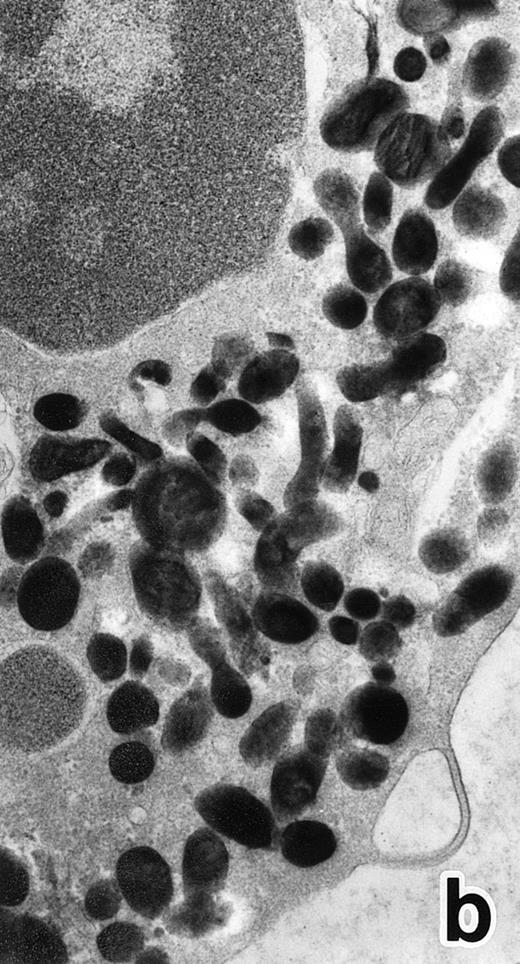

(a) A bone marrow leukemic cell in patient no. 1 at diagnosis containing abundant abnormally shaped primary granules, including Auer rods and Chediak-Higashi–type inclusions. Dilatation of rER is remarkable. (Original magnification × 10,800.) (b) Higher magnification of a cytoplasmic inclusion body of another cell in patient no. 1 that is membrane-bound and contains bundles of filamentous structures, similar to Auer rods. (Original magnification × 25,800.)

Electron microscopic observation.The leukemic cells of all three patients possessed abundant spherical (type I) primary granules containing electron-dense homogeneous material, with a peripheral halo in some granules and dilated rER (Fig 2a). Although type I primary granules predominated in all patients, small numbers of cytoplasmic granules containing crystalloid structures (type II primary granules) were also present in patient no. 1. Nuclear configurations were irregular, and the chromatin was only slightly condensed along the nuclear membrane. In addition to numerous Auer rods, the cells of patient no. 1 contained large cytoplasmic inclusion bodies also seen under the light microscope. These are the structures surrounded by a unit membrane and filled with parallel tubular material identical to that of Auer rods and belong to the psuedo–Chediak-Higashi (C-H) category of granules20,27 (Fig 2b). The cells of patient no. 3 contained smaller cytoplasmic granules than those of the other patients, and Auer rods were less frequently observed, a finding consistent with the M3 variant. Stellate rER complexes and fibrillar structures in the rER, both of which are thought to be structures specific to APL,28 were detected in this patient.